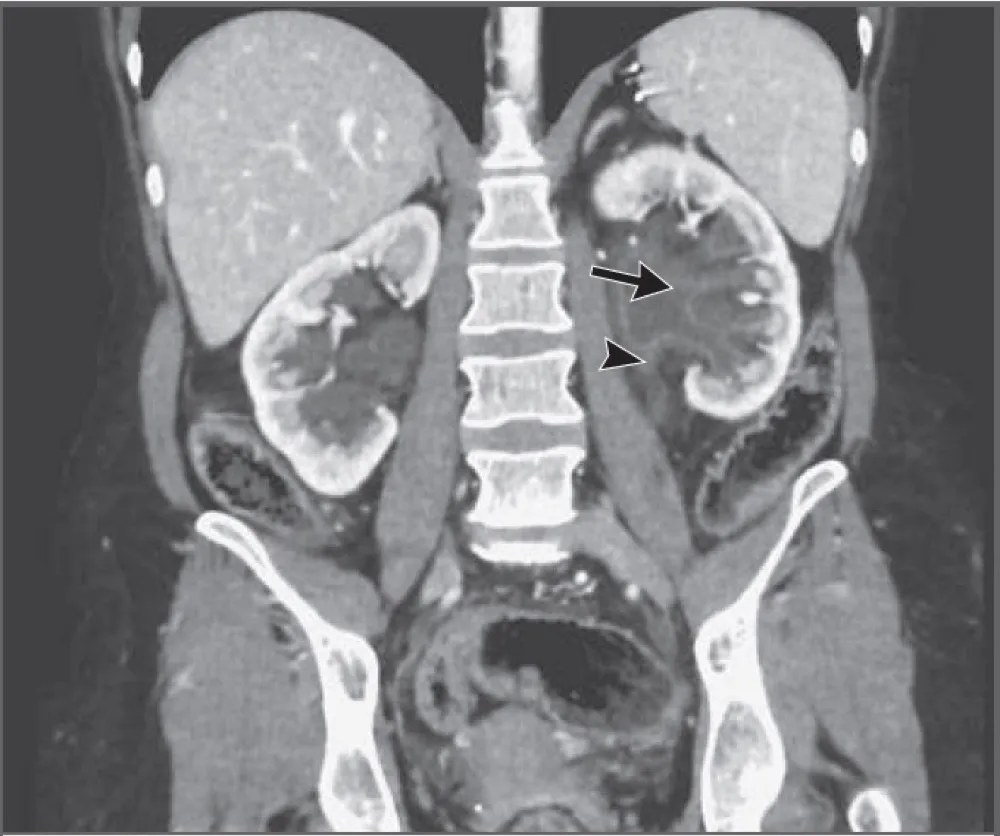

Hematuria e perda rápida da função renal em pacientes com câncer devem levantar suspeita de trombose da veia renal, mesmo sem contraste. Imagens não contrastadas e Doppler podem ser ferramentas-chave nesse contexto.

Valkercyo Feitosa

2 anos atrás